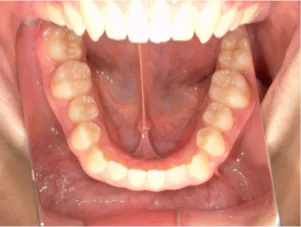

治療中③中1:拡大・前歯の並替え、トイシャー(出っ歯を治す装置)終了

*出っ歯、過蓋咬合、口唇閉鎖不全の改善

*咬合治療用モノブロック装置(筋機能的咬合誘導装置)へ移行

*口唇閉鎖不全がなおり奇麗な口元に改善

*就寝時に使用するモノブロック装置(筋機能的咬合誘導装置)